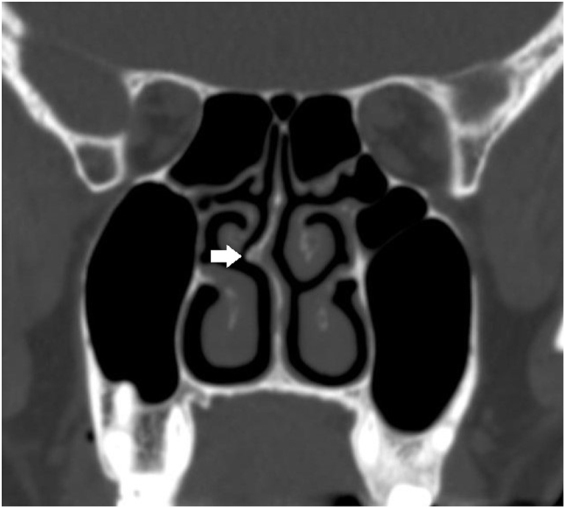

Abstract Image